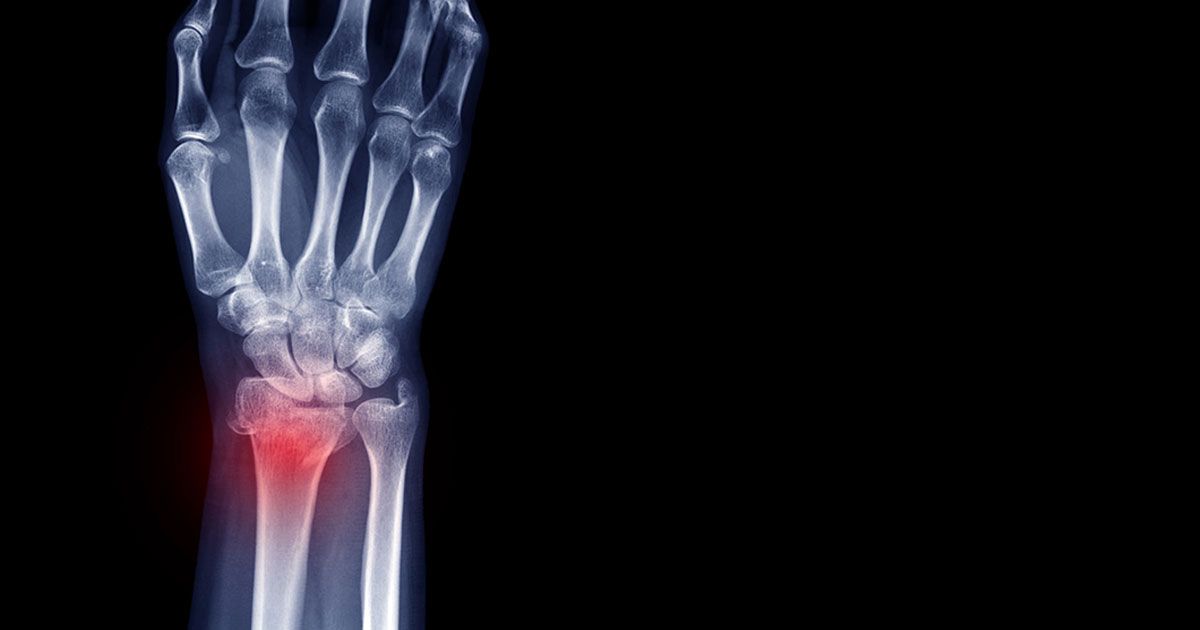

Ad oggi, quando si parla di frattura di Colles, si identificano tutte le fratture relative all’estremità distale del radio. Questo osso costituisce con l’ulna lo scheletro dell’avambraccio. La frattura in questione comprende tutte le lesioni di quello definito polso, ovvero quella comprensiva del carpo scafoide e semilunare.

Questa lesione è conosciuta anche con altri nomi tecnici, quali frattura trasversa del polso, frattura del radio distale, frattura “a baionetta” e frattura “a dorso di forchetta”. È caratterizzata da un dolore persistente che impedisce a chi ne è colpito di afferrare oggetti senza avvertire un dolore. Può inoltre presentarsi anche un gonfiore e un’ecchimosi nella zona interessata.

Se in seguito ad una caduta si verifica una situazione di dolore e gonfiore in prossimità del polso è indicato procedere con una diagnosi accurata finalizzata all’identificazione della frattura di Colles. Questa, con i moderni mezzi ospedalieri a nostra disposizione, può facilmente essere individuata in seguito ad una radiografia a raggi X.